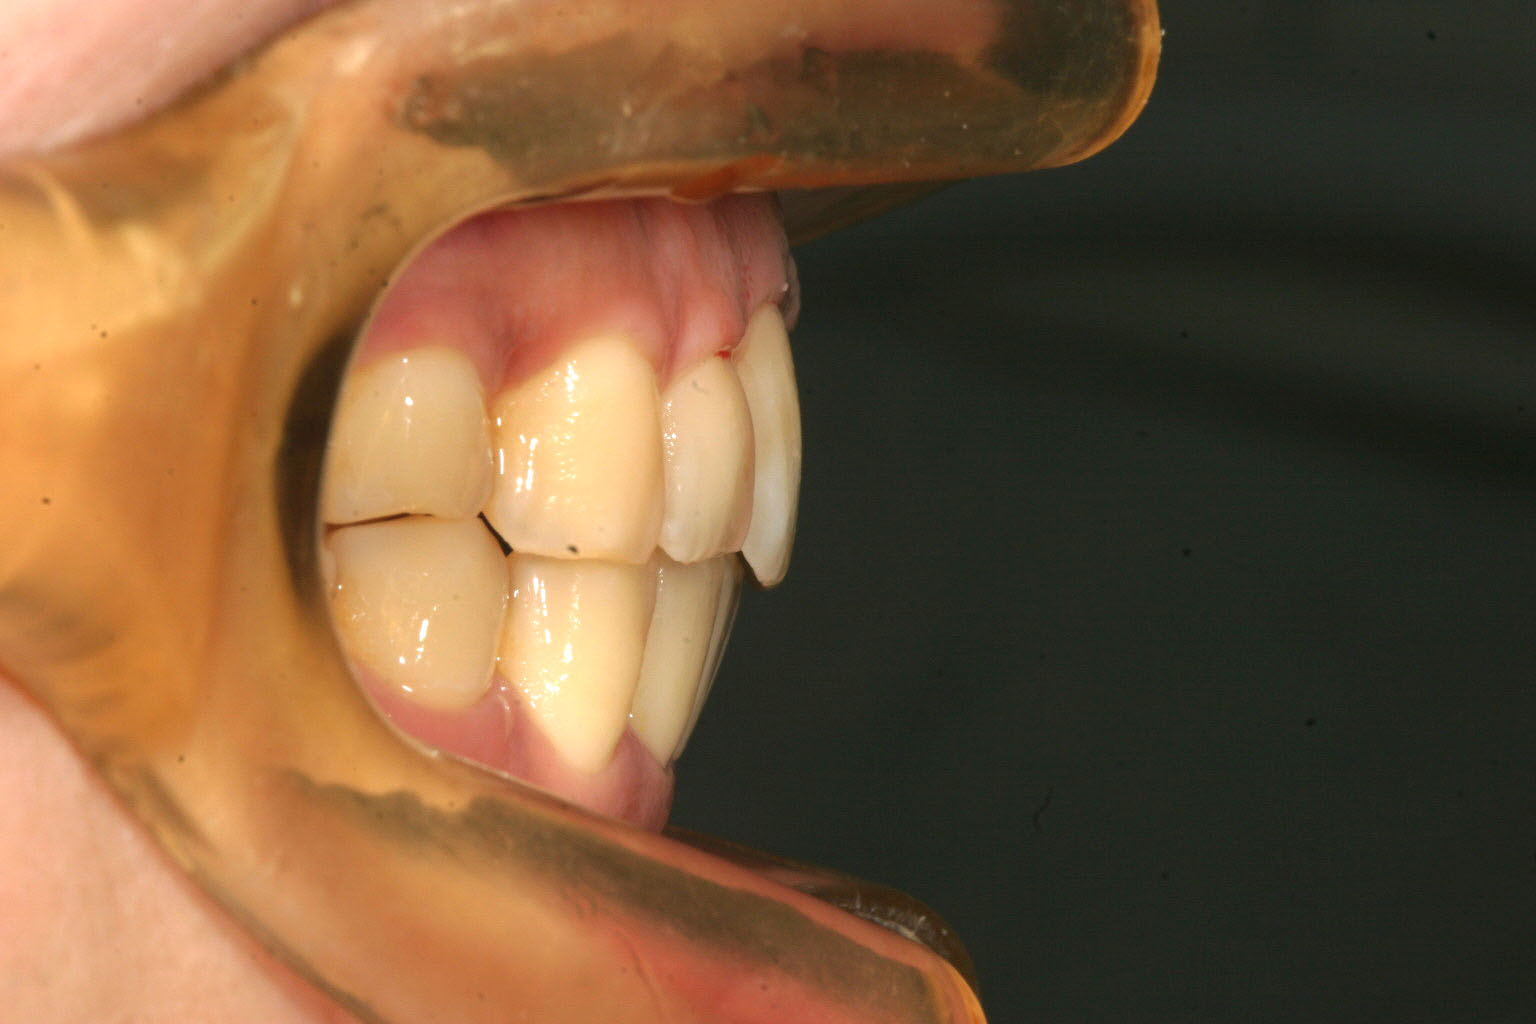

完全に出っ歯が改善しました。

前回の写真と比較しますと分かると思うのですが抜歯しなくてもここまでの改善が出来ます。

これはインビザラインの機能であるIPR(歯と歯の隙間を削る)と言う方法を使う事によりでっぱをここまで改善致しました。